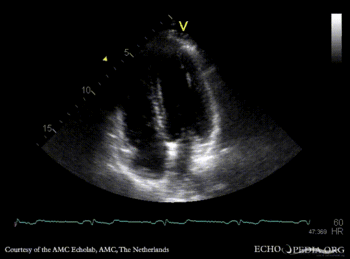

| A4CH with contrast: right to the left shunt | |